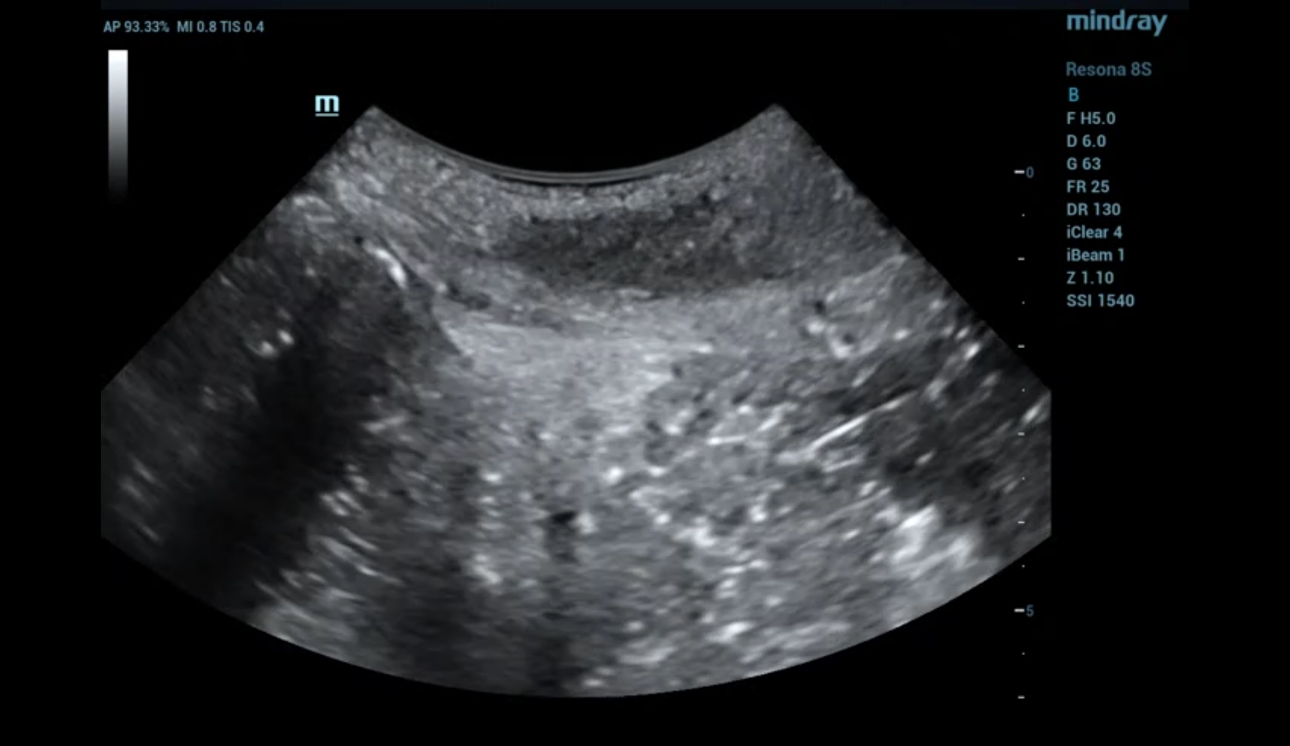

?? ?? ????? parasagittal view??? ???/?? 2D ???, 3D/4D ?? ??, Ipage+?? ?? ?? ?? ???? ?????.

- 2D ?? : ???? ??? ?? ?? ???? interruption? ?? ???? ??? ?? ??? ??.

- Levator hiatus? ?????? ?? ????? ?? ??.